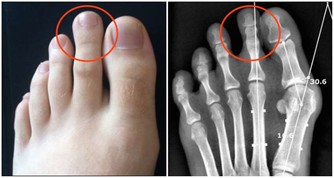

當人出現腳氣、四肢浮腫、消化不良、血壓下降等症狀時,很有可能缺少維生素B1。